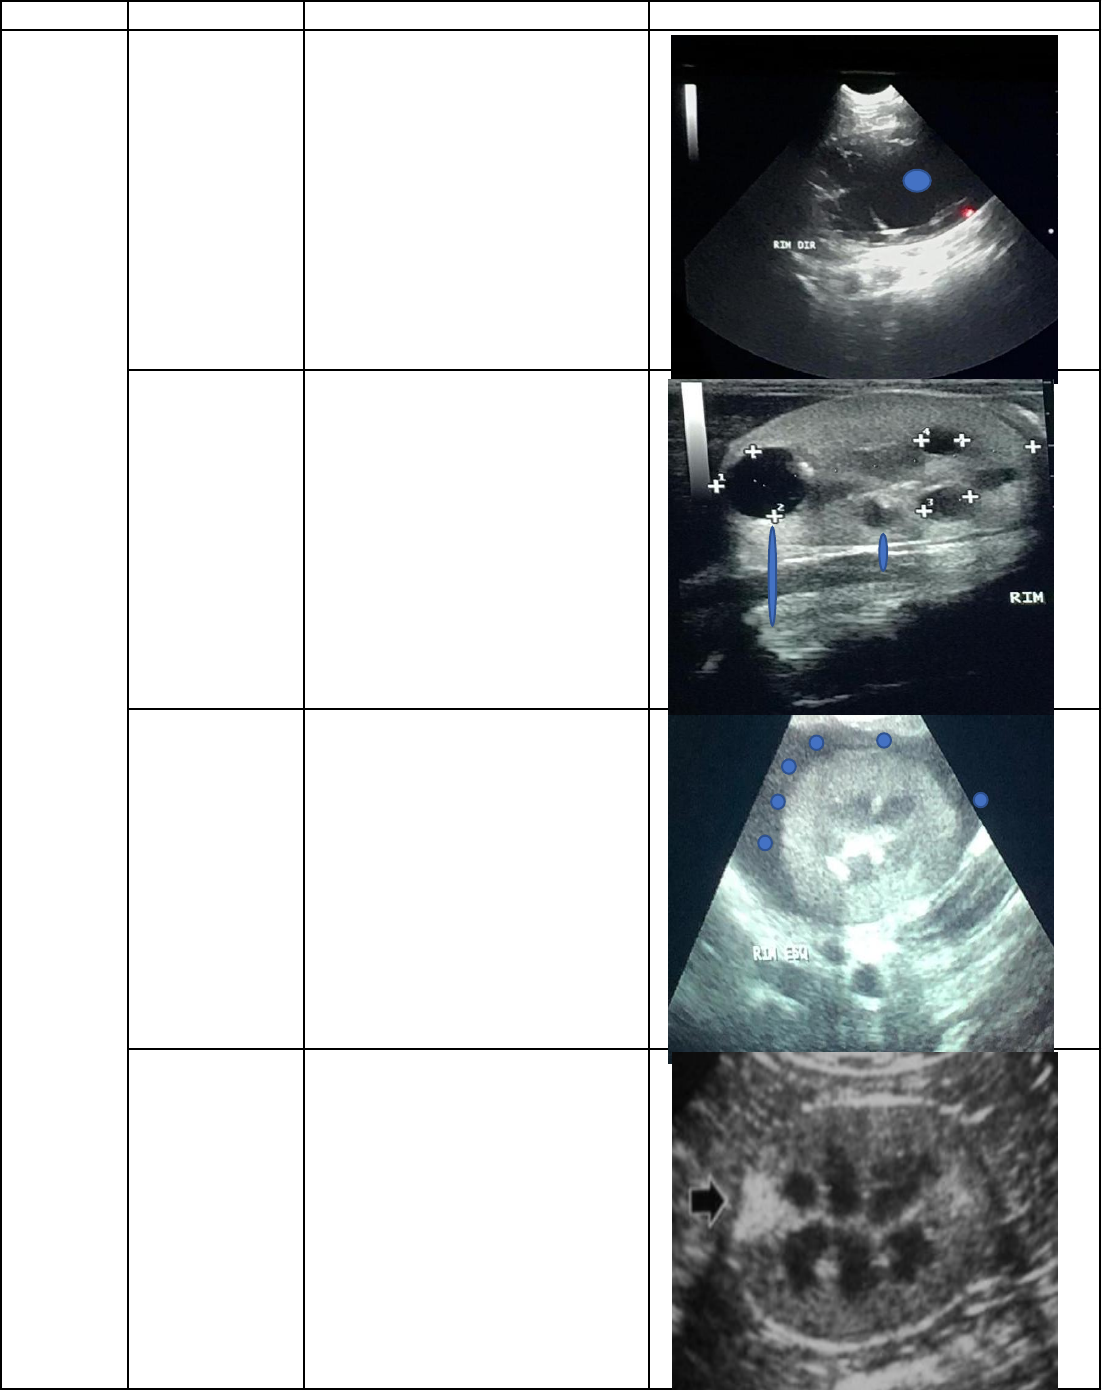

CATEGORIA DOENÇA DESCRIÇÃO FOTO

HIDRONEFROSE/D

ILATAÇÃO DA

PELVE

Perda de definição da pelve por

dilatação da mesma (hidronefrose),

tornando-se uma grande área de

anecogenicidade (preta) (por conta

do liquido) marcada na foto ao lado

pelo ponto azul

CISTO OU RIM

POLICISTICO

Áreas arredondadas anecogenicidade

(pretas) no interior dos rins com

reforço acústico indicadas ao lado,

de azul

PSEUDOCISTO

PERIRENAL

É uma área anecogênica (preta)

entre a cápsula e o parênquima

renal. Essa área vai estar abraçando

o rim

ÁREAS DE

INFARTO

Área hiperecogenica em formato de

cunha (triangulo) como indicado na

foto ao lado, na região onde ocorreu

o infarto